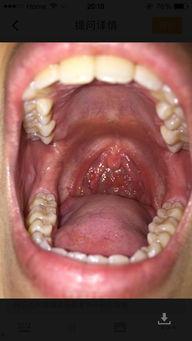

3. 口腔溃疡:小白瓜中的酸性物质可能会刺激口腔溃疡,导致喉咙痛。

4. 喉咙炎症:如果你本身就患有喉咙炎症,吃了小白瓜后可能会加重病情,导致喉咙痛。